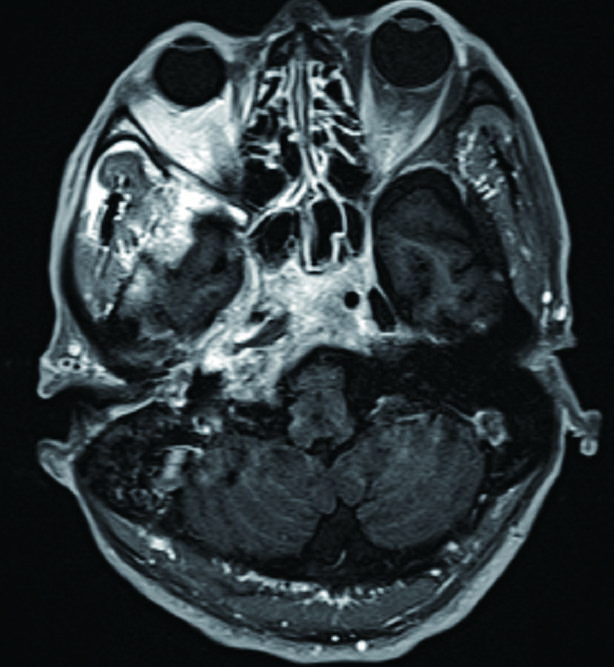

1 资料与方法病例1,患者男性,66岁,因头痛3周,复视1周入院。患者3周前起右侧太阳穴针刺样疼痛,影响睡眠。2周前出现咽痛鼻塞流涕及双耳听力下降,伴有右侧额部皮肤红疹,上述症状在当地医院治疗后减轻。1周前出现复视,当地医院治疗后症状无好转,诊断:颅内感染,多颅神经麻痹转来本院急诊。查体:神清,面部可见散在淡色丘疹,以右侧前额为主,右眼外展受限,面部痛触觉无殊,四肢肌力5级,病理反射阴性。脑脊液生化常规示:潘氏试验阳性,有核细胞970/μL;血沉28.00 mm/h,C反应蛋白14.1 mg/L。增强头颅MR提示两侧海绵窦增粗增宽,考虑炎症,并见双侧筛窦上颌窦蝶窦炎(图 1)。予头孢曲松钠2.0 g静脉注射抗感染治疗。治疗2周后头痛明显减轻,但复视症状无好转。复查血常规正常,C反应蛋白正常范围,血沉28.00 mm/h,脑脊液生化及常规正常范围。复查头颅增强MR提示病变范围较前无缩小。鼻窦CT提示双侧蝶窦炎症较前加重(图 2)。建议患者行鼻内镜下蝶窦手术。患者自觉症状减轻拒绝手术,要求出院。出院后在外院继续头孢曲松钠抗感染治疗。治疗10 d后因头痛复视症状无改善,并出现面颊部感觉减退再次入院。入院后查血常规,C反应蛋白正常,血沉28.00 mm/h,脑脊液潘氏试验阳性,细胞数量继续减少至60/μL。继续抗感染治疗。再次头颅MR及鼻窦CT复查提示海绵窦及蝶窦内病变较前范围增大(图 3),经多学科讨论,转本科行视频内镜下双侧蝶窦开放术。术后第三天鼻腔填塞物完全抽除后头痛症状明显缓解,术后6 d出院,头痛症状消失,复视仍存,出院后继续抗感染治疗,定期门诊复诊,术后6个月,复视症状消失。

| 图 1 双侧海绵窦增宽,右侧明显 |